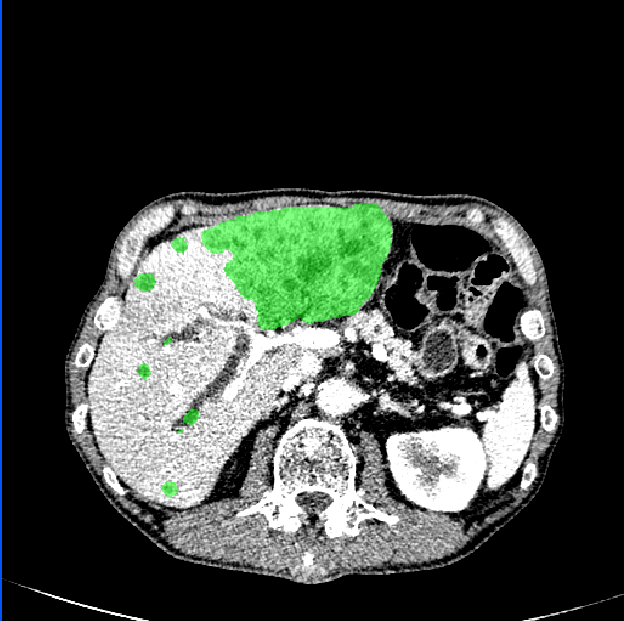

3.1 Comparison of Various Distance Maps Regression

A simple illustration of distance maps is shown in Fig. 2, which contains the binary segmentation mask, O-DM, inverse distance map (I-DM), NI-DM and sign norm inverse distance map (SNI-DM). I-DM is derived from the I-DM by taking inverse operation. SNI-DM is modified from the NI-DM, where the voxel inside the boundary of the target object is positive, otherwise is negative.

To analyze the learning behavior of our method with different distance maps, we conduct several comparative experiments on the LiTS training dataset and the results are reported in Table 1. Notably, we adopt different activation functions of the LR-Net output layer according to the nature of distance maps. In brief, the O-DM and I-DM regression employ ReLU activation; the NI-DM regression uses both ReLU and Sigmoid for comparison purposes; the SNI-DM regression employs Tanh activation. We take the M-Net with Dice loss and MapDice loss as two baseline methods, yielding a Dice score of 0. 6581 and 0.6856, respectively.